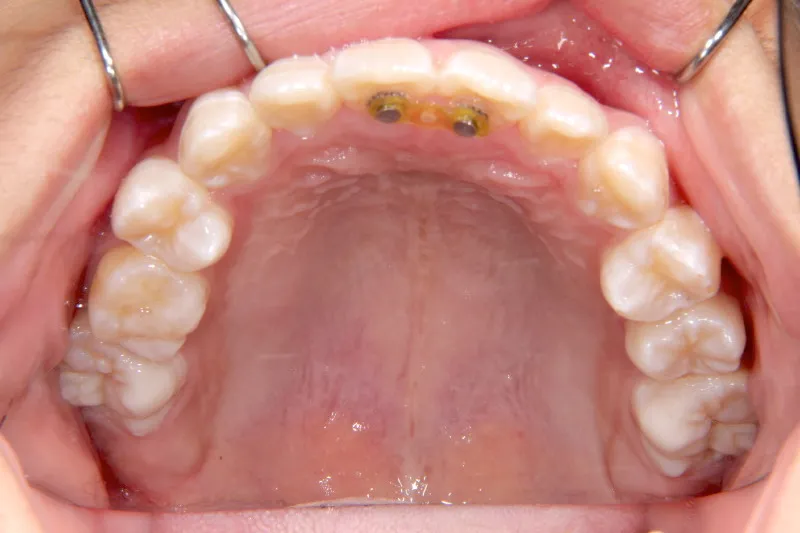

【子供の矯正(一期)】叢生・開咬・前歯で噛めない・舌癖・7歳女児【M.O様】

初診時年齢 小学校1年生 (女性) 主訴 前歯で噛めない

診断名 叢生・開咬 装置名

拡大床

舌の癖によって下の前歯が出て、上の前歯が短いです。

取り外し式の装置で上下の歯並びを拡げて、下の前歯を引っ込めます。

初診